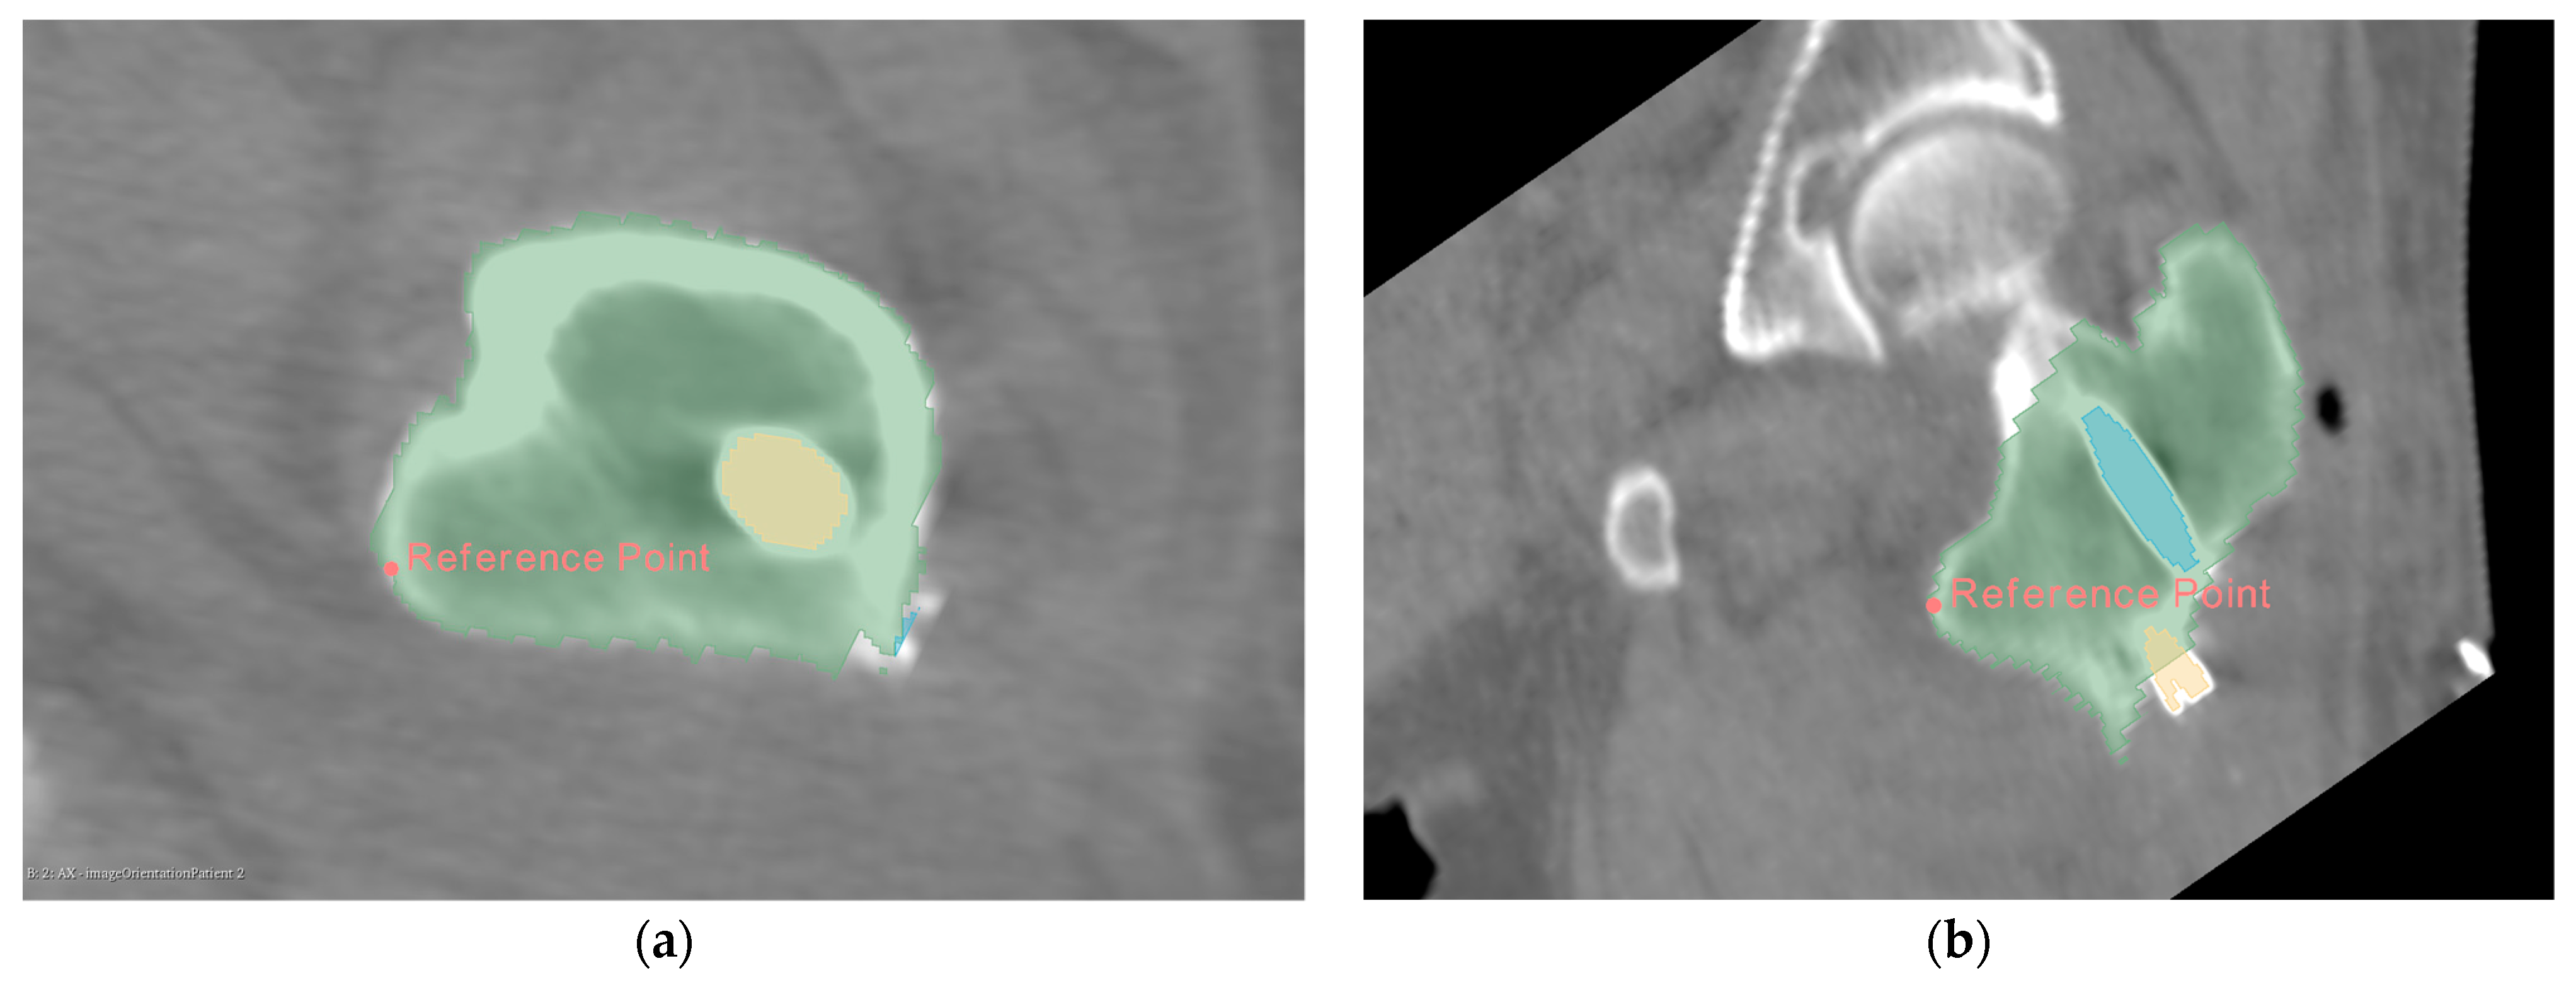

3.3. Calculation of Implant Displacement

Using principal component analysis, we built the pins’ outer bounding box, obtained the coordinates of the endpoints of the four pins in Figure 11 separately, and calculated the displacement of the corresponding points. To analyze the displacement of Hansson pins more comprehensively, we take the axis of pins as the z axis, the direction of hook extension as y axis, and the direction of the cross product of y and z as x axis to establish a new coordinate system, as shown in Figure 12a,b are the proximal pin and distal pin coordinate systems, respectively. In the new coordinate system, the proximal pin and distal pin’s displacements in different directions are calculated.

Figure 12.

Calculate the displacement of the proximal pin and the distal pin in the specified direction in the newly established spatial coordinate system: (a) establish the coordinate system based on the proximal pin; (b) establish the coordinate system based on the distal pin.